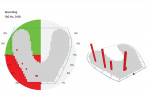

The clinician started by recording a set of diagnostics, which included radiographs, an intraoral scan, photographs, and an OccluSense reading. The initial reading showed that the patient had only a few true points of contact, with much heavier occlusion on the left side of her mouth (Figure 2). Because the patient was in temporary crowns when she presented to the office, a combination of additive dentistry and reduction was used to facilitate a more stable occlusion. An intraoral scan was then taken to record this occlusion, and a new set of temporary crowns were fabricated, with care taken to maintain the occlusion that had just been created.

The patient remained in the temporary crowns for a few weeks, during which time she was brought back into the office once to adjust the occlusion, with the OccluSense used as an aid. When the patient was comfortable and happy with her bite, one more intraoral scan was taken so that the final restorations could be made in an occlusion that was acceptable to her (Figure 3 and Figure 4). Using the OccluSense to clearly identify where the occlusion was unbalanced enabled the clinician to take the patient out of discomfort and create a solution for her complex case.